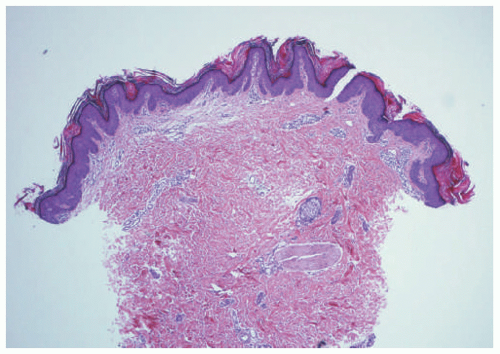

![]() FIGURE 23-2. Epidermal nevus frequently resembles seborrheic keratosis histologically, with orthokeratotic hyperkeratosis, papillomatosis, and epidermal acanthosis. |